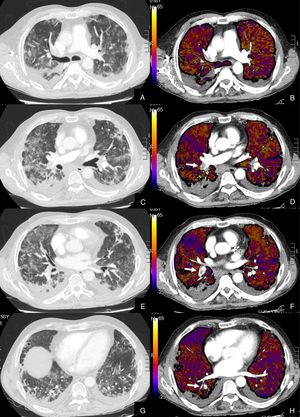

Paciente con COVID-19 que después de una semana de ingreso hospitalario persiste con desaturación que no corrige con flujo elevado de O2.

Imágenes axiales de la angiografía pulmonar con TC y mapa de yodo en ventana de parénquima (A, C, E, G) desde el cayado aórtico hasta los lóbulos inferiores y su correlación con el mapa de yodo (B, D, F, H).

Parénquima con afectación severa en vidrio deslustrado de predominio subpleural y segmentos posteriores de todo el pulmón, sin TEP visible. El mapa de yodo muestra una severa hipoperfusión difusa de todo el pulmón tanto afectado como sano (zonas azules y negras) en probable relación con microtrombosis difusa del lecho capilar.